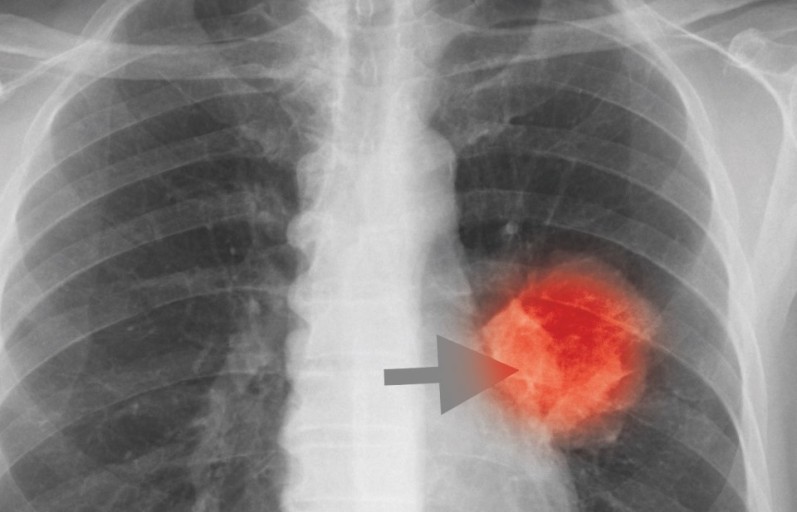

폐암 초기증상 가래에 피가 섞여 나옴 (객혈)

- 설명: 붉은색이나 녹슨 철 색깔의 피가 가래에 섞여 나오거나, 심한 경우 기침할 때 피만 나오는 증상입니다. 이는 폐암이 혈관을 침범했을 때 나타나는 중요한 경고 신호입니다.